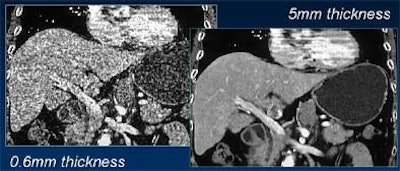

| Comparable image quality is seen in thick axial reconstructions of images acquired at 1.25-mm (upper left) and 2.5-mm collimation (upper right). However, coronal reformations of the pancreatic duct are markedly sharper from 4 x 1.25-mm data (lower left) compared with image acquired at 4 x 2.5 mm (lower right). SC = slice collimation, TF = table feed, P = pitch. Images courtesy of Dr. Mathias Prokop. |